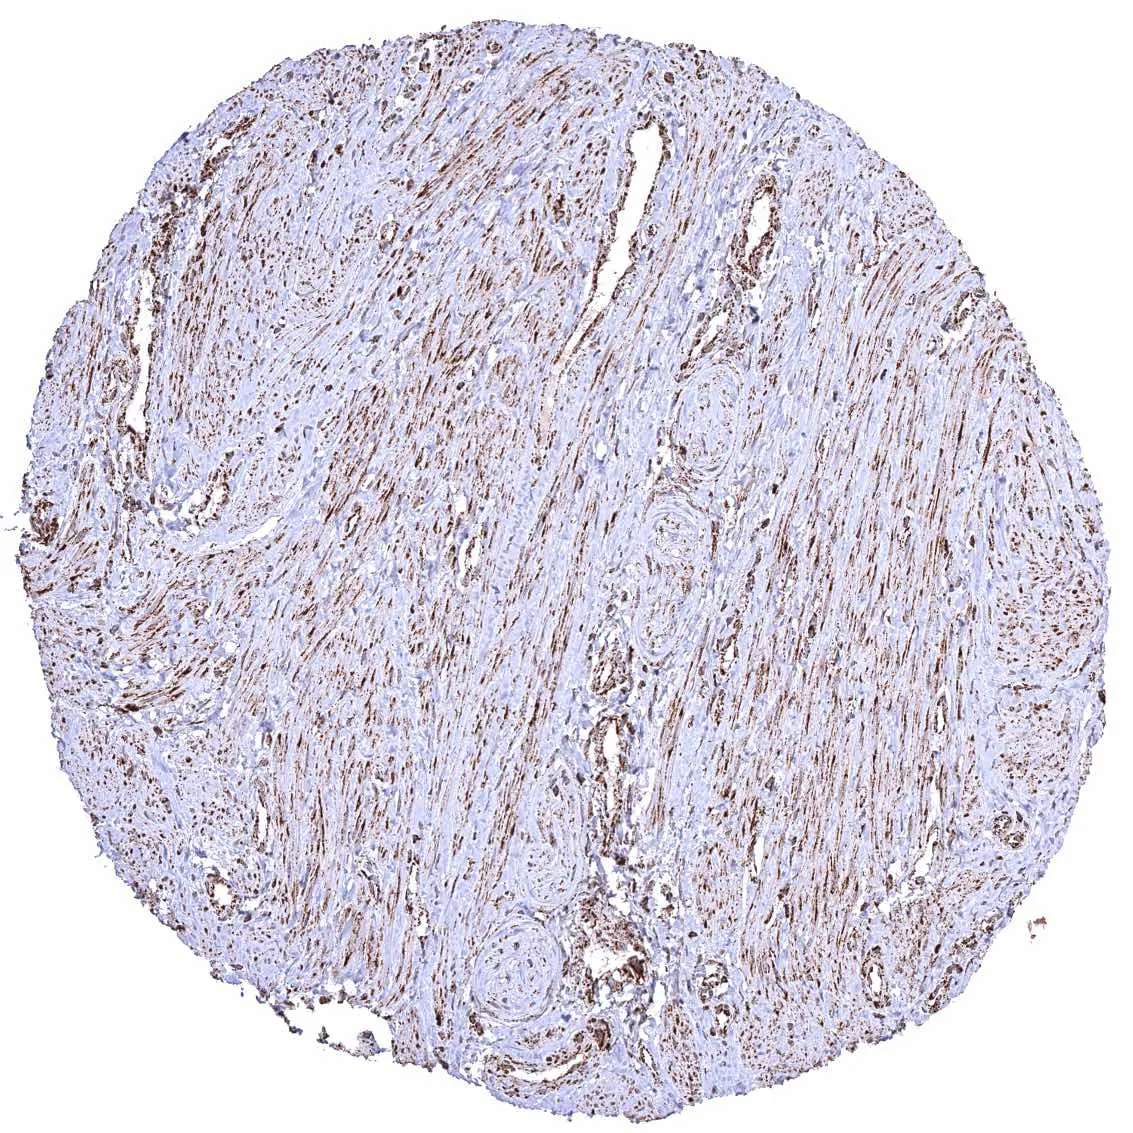

Urinary bladder, muscular wall